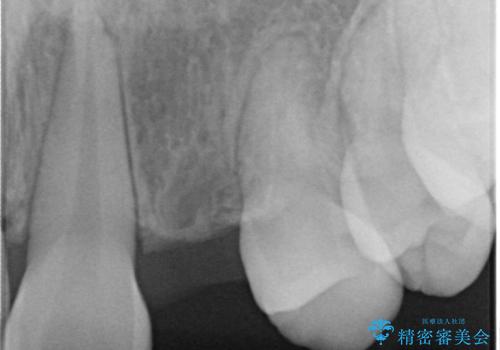

- 歯列矯正後に前歯にブリッジを入れた方の経過です。

矯正治療の術前後の経過は以下をご覧ください。

矯正治療で歯の位置を整えてからブリッジを入れると歯の幅を自由に設定できるため、左右対称にできます。結果矯正なしでいきなりセラミックにする場合と異なり、無理に角度を変えたりする必要がなく、神経をなるべく温存したまま審美的なセラミック治療が行えます。